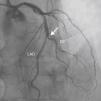

A 69-year-old man was referred for PCI of a 90% calcified lesion in the mid left anterior descending artery (LAD) involving the second diagonal branch (D2; Figure 1, arrow). After the left coronary ostium was cannulated and crossed with two BMW® wires, one to the LAD and other to the D2, predilation with a 2.5 mm×15mm Trek® balloon was performed and an unsuccessful attempt was made to cross the stenosis with a 2.75 mm×22mm Resolute Integrity® drug-eluting stent. Predilation was repeated with a 2.75 mm×15mm Trek® non-compliant balloon at high pressure. Suddenly, balloon rupture was detected and the angiogram showed LAD rupture with extensive contrast extravasation into the pericardium (Figure 2, arrows; Video 1). Protamine sulfate was used to reverse the effect of heparin and the drug-eluting stent was deployed with balloon inflation for 10minutes to seal the type III perforation but, as dye extrava- sation persisted, a 3.0 mm×19mm GraftMaster® covered stent was superimposed, followed by rapid cessation of contrast leakage (Video 2). The D2 branch was lost (Figure 3, arrows), and periprocedural myocardial infarction occurred. The final image showed pericardial effusion (Figure 4; Video 3). The echocardiogram excluded tamponade. Forty-eight hours later, atrial fibrillation occurred with hemodynamic deterioration. Pericardiocentesis was performed and 50ml of serosanguineous fluid was drained. Sinus rhythm was restored, with favorable evolution thereafter.